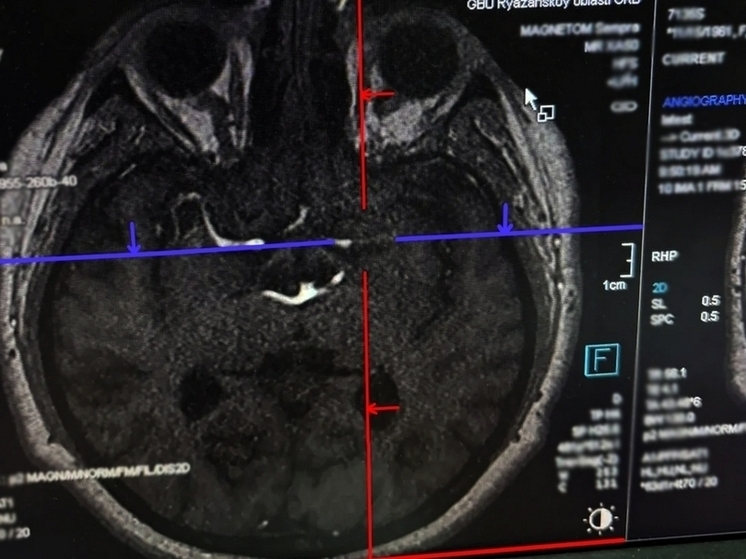

Фото: минздрав Рязанской области

Врачи рязанской ОКБ спасли 24-летнего молодого человека, который перенес инсульт. Об этом сообщает региональный минздрав.

Рязанец покурил вейп и у него потемнело в глаза, закружилась голова, и он потерял сознание. Врачей вызвала подруга молодого человека. В больнице ему провели тромболитическую терапию, после чего пациент смог вставать и двигаться.